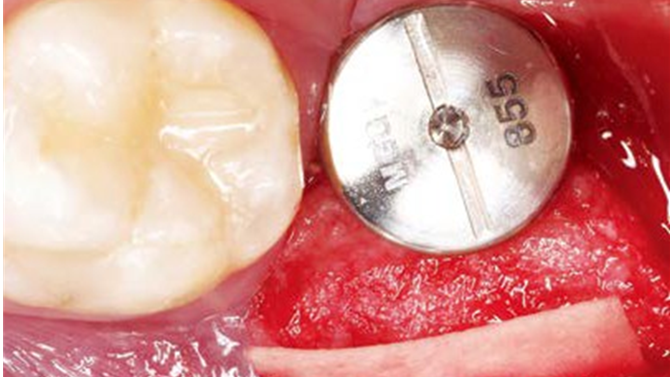

Clinical case: Bone filling into the bottom of deepest thread at 8.0mm AnyRidge fixture

- Courtesy of Dr. Kwang Bum Park -

Keywords

AnyRidge, Knifethread ,extraction socket, ,initial stability ,Allograft, ,osseointegratio ,Dr. Kwang Bum Park, , Mandibular, Single replacement, AnyRidge, Mega-oss,

Products used

Implant system-AnyRidge, Regeneration-Mega-Oss